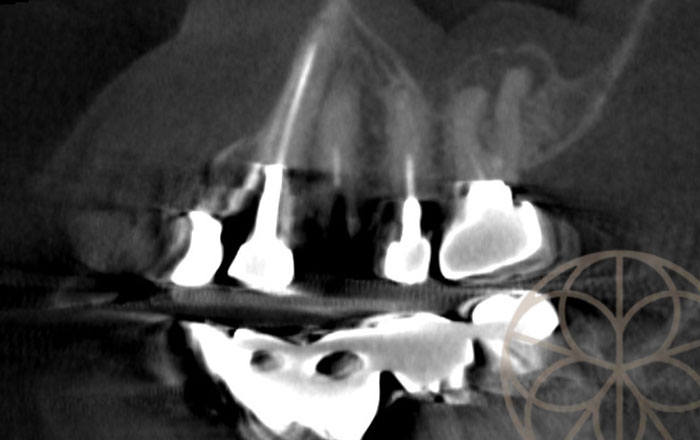

治療前CT写真

CTでは、外側には、骨が少ないですが、根の先の部分と内側には、十分に骨があると判断し、抜歯して、同時にインプラント埋入する抜歯即時埋入インプラント(ワンデーインプラント)が可能であると診断しました。